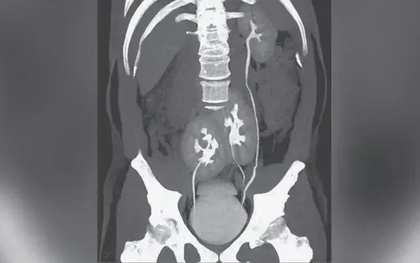

Đi khám nhiễm trùng tiết niệu, người đàn ông 31 tuổi phát hiện có 3 quả thận

Bệnh nhân thậm chí không bao giờ nhận ra mình có thêm một quả thận trong suốt cuộc đời.